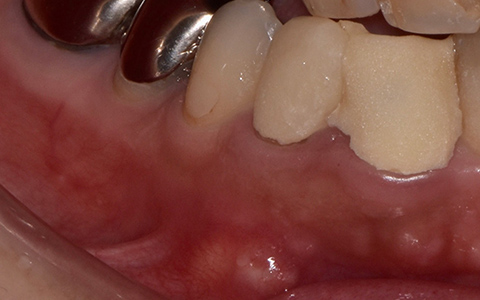

治療前

治療後

写真の白丸部分に膿が溜まっていて痛みと腫れがあり、半年も続いているそうです。これを治療した歯科医師はこれで治らなかったら抜歯してインプラント治療という選択をしました。

歯の状況や、顎骨の状況、また、患者さんご自身からもできるだけ自分の歯を残したいというご希望だったので、精密根管治療を天然歯の保存を目的として計画しました。

まず、根管内のガッタパーチャ(根管充填材)を除去、さらにマイクロスコープによる拡大視野とラバーダム防湿法により丁寧に汚れを除去しました。根管内の感染源がなくなったことを確認したうえで、通常のガッタパーチャとシーラーでは緊密な根管充填ができないと診断し、患者さんに説明したうえでMTA (ProRoot MTA)を選択しました。

3回の治療を行った後、痛みと腫れ、また上の画像にあった丸印の膿の袋もなくなっています。ということは、インプラントせずにこの上にクラウンを被せて治療を終了することができます。

| 費用 | コア除去:22,000円 根管治療:132,000円 MTA根管充填:33,000円 合計:209,000円 |